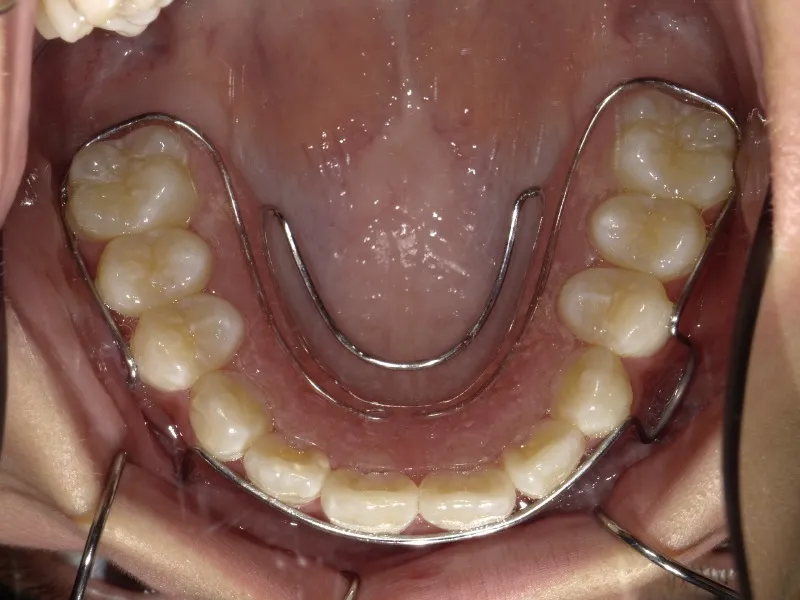

診断名 叢生 装置名

拡大床

抜歯の有無 非抜歯 治療期間・通院回数 7年 4ヶ月 / 43回

状態 永久歯が生える隙間がない(叢生)

ガタガタ・でこぼこに生えている(叢生)